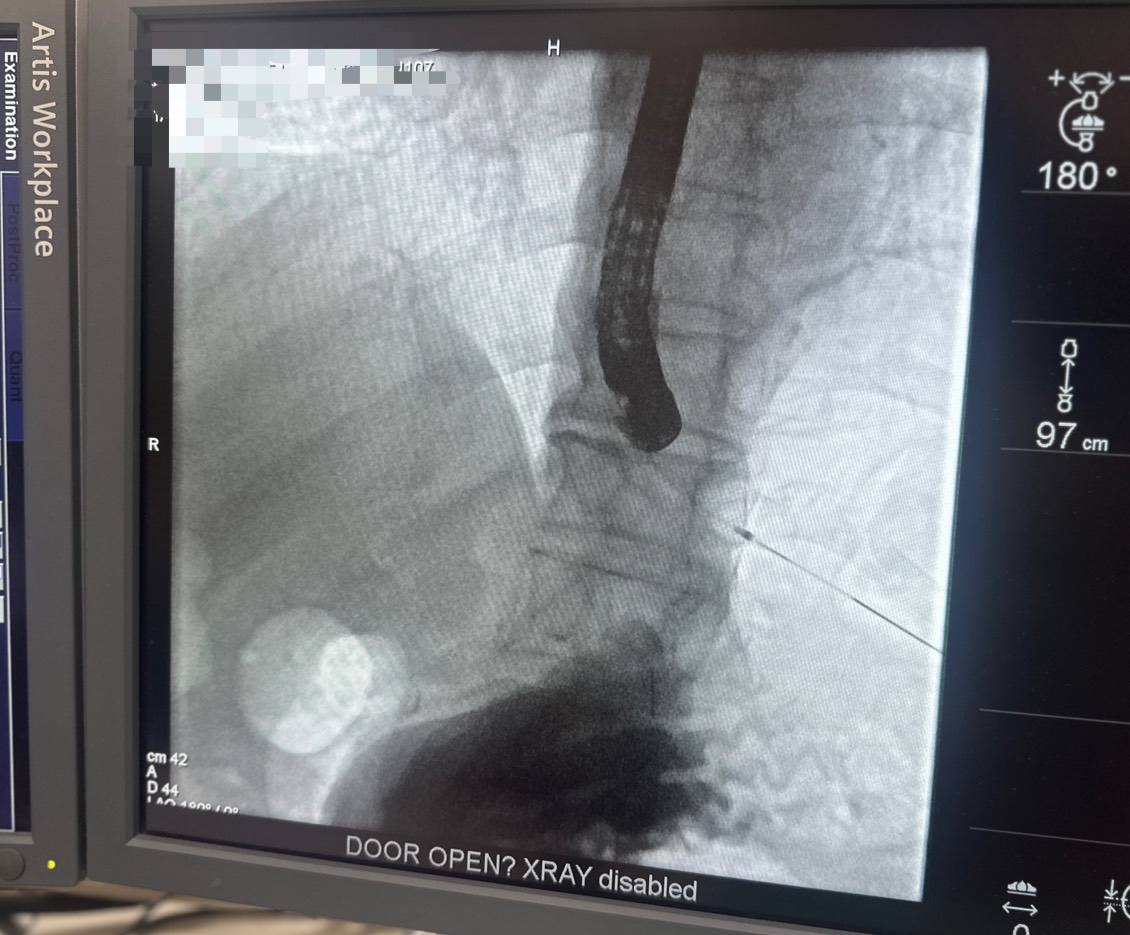

▲急性膽管炎恐惡化成敗血症或休克,嘉榮肝膽腸胃科主治醫師呂家嘉執行微創ERCP取出阻塞結石,救回一命。

▲ERCP檢查影像不需開腹即可取出結石。臺中榮總嘉義分院肝膽腸胃科呂家嘉醫師進一步說明,ERCP 雖屬侵入性處置,術後最常見的併發症為胰臟炎,發生率約為3.5至9.7%,其他如膽管炎、出血或穿孔等併發症,發生率5~10%,致死率約0.3~1%(多為複雜式高風險病患)。醫師會在術前依病患年齡、身體狀況、感染嚴重程度與共病情形進行完整評估,並與病患及家屬充分討論治療策略與風險控管方式,選擇最適合的微創處置。術後也由專業醫療團隊密切監測,使多數患者能安全完成治療、順利恢復。 (圖:劉芳妃翻攝)